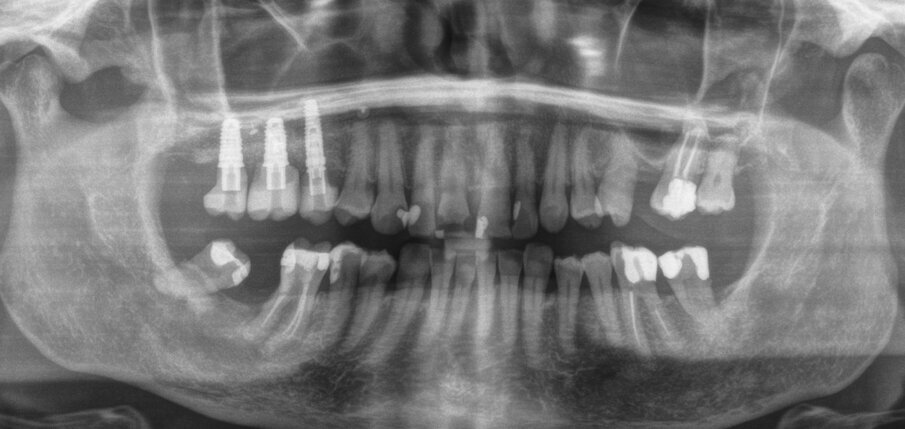

Dopo 9 mesi, è stata eseguita una seconda CBCT per valutare il volume di osso rigenerato e per pianificare la chirugia computer guidata (Fig. 23); i file .STL ottenuti dalla scansione 3D e i files .DICOM della CBCT sono stati utilizzati per pianificare l’inserimento degli impianti tramite una chirurgia computer guidata (Navimax, Biomax) (Fig. 24) . Il giorno della chirurgia implantare (T1), è stata eseguita un’incisione orizzontale para-crestale, per permettere l’esposizione della griglia e la sua rimozione, previa rimozione delle viti in titanio e dell’osso formatosi al di sopra di essa (Figg. 25, 26). L’esame clinico ha evidenziato una completa rigenerazione ossea del difetto osseo verticale, con assenza di pseudo-periostio o pseudo-periostio minore di 1 mm, di conseguenza pseudo-periostio di “classe 1” secondo la classificazione di Cucchi et al.20 (Figg. 27, 28). Successivamente, la dima chirurgica è stata posizionata e fissata nella posizione pianificata; i siti implantari sono stati preparati con frese progressive dedicate; e tre impianti conici (T3, Zimvie) sono stati inseriti nelle posizioni #15, #16 e #17, secondo la pianificazione protesicamente guidata eseguita precedentemente mediante il software da chirurgia guidata (Figg. 29-31). Gli impianti sono stati “sommersi”, attendendo la corretta osteointegrazione, ed è stata eseguita una chiusura per prima intenzione (Fig. 32). Dopo il posizionamento degli impianti, è stata eseguita una radiografia OPT (Fig. 33).

Dopo 3 mesi (T2), gli impianti sono stati esposti mediante un lembo spostato apicale per aumentare la quantità di tessuto cheratinizzato vestibolarmente agli impianti e riallineare la linea mucogengivale precedentemente spostata in direzione palatale; e sono state applicate viti di guarigione svasate per favorire una corretta guarigione trans-mucosa. Dopo 1 mese (T3), sono state eseguite corone singole in ceramica, per il primo carico funzionale e la finalizzazione provvisoria del caso, in attesa della maturazione ossea completa (Fig. 34). Dopo 6 mesi (T4), le corone sono state sostituite con corone in zirconio, per il carico funzionale e la finalizzazione definitiva degli impianti (Figg. 36-38). I controlli clinici e radiografici al primo carico funzionale, a 6 mesi, a 12 mesi, e a 24 mesi, mostrano la salute dei tessuti peri-implantari e il mantenimento dei livelli ossei peri-implantari (Fig. 39).